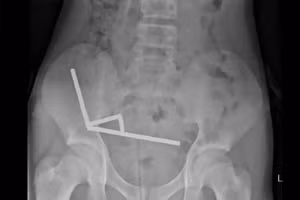

GD&TĐ - Ngày 16/4, Bệnh viện TP Thủ Đức (TPHCM) cho biết vừa tiếp nhận bệnh nhi N.N.N.Y (5 tuổi) nuốt phải nam châm hình ngôi sao trong lúc ăn cơm.